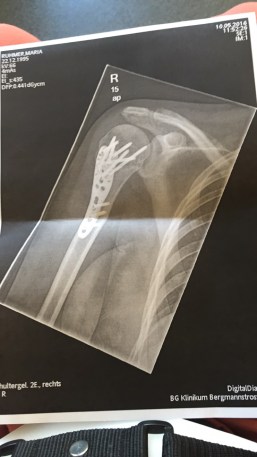

Darf ich vorstellen – mein Oberarm! Sieht irgendwie aus, als hätte hier jemand seine Wut ausgelassen. Mit einer Platte und zehn Schrauben verließ ich den Op und durfte meinen Arm wieder bewegen. Das machte anfangs meine Physiotherapeutin Laura, später dann auch mein Papa. Irgendwann fing ich dann selbst an zu trainieren. Der Arm tat sehr lange weh und brauchte ziemlich viel Zeit um wieder belastbar zu sein.